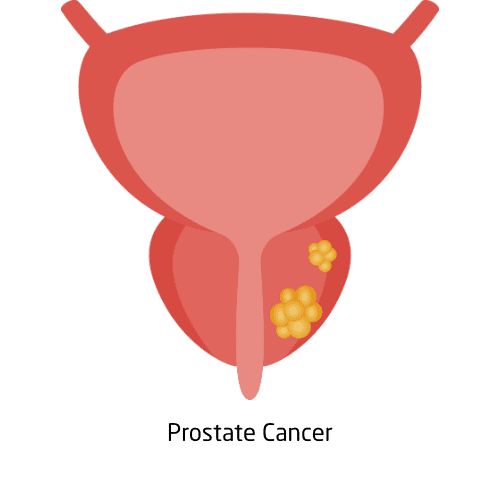

Prostate cancer begins in the prostate gland, which is part of the male reproductive system. It’s one of the most frequently diagnosed cancers in men, especially those over 50. In its early stages, it may not show symptoms, but advanced cases can cause difficulty urinating, blood in urine, or pelvic pain. Routine screening, such as the PSA (prostate-specific antigen) test and digital rectal exams, helps detect it early.

Treatment options range from watchful waiting to surgery, radiation, hormone therapy, or newer targeted treatments depending on the cancer’s growth rate and spread. Support groups and resources are available to help patients navigate diagnosis and recovery.